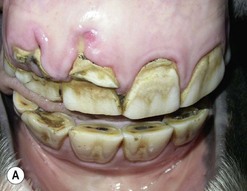

Amelogenesis imperfecta includes a range of hereditary disorders affecting enamel formation in both deciduous and permanent teeth and can be divided into two types, i.e., defects in enamel matrix formation or in the mineralization of enamel. The genetics of this disorder in particular are well studied in human dentistry, with AMELX gene mutations increasingly described.9,30 Amelogenesis imperfecta as part of a generalized ectodermal syndrome has been described in a horse (Fig. 8.14),10 and an amelogenesis defect is also the likely cause of the widespread dental dysplasia present in the horse shown in Figure 8.15.

image

Fig. 8.14 Severe dental dysplasia with some abnormally small sized (microdontia) and misshapen CT, and concurrent hypodontia in a young Thoroughbred that suffered a generalized ectodermal dysplasia.

(From Ramzan et al10 with permission from Equine Veterinary Journal.)

A wide range of developmental defects of dentin has been described in humans including dentinogenesis imperfecta and others caused by mineral and vitamin deficiencies. Developmental cemental defects are less commonly described in any species, and include root hypercementosis, a feature so commonly found in older equine teeth as to be almost regarded as physiological. Marked hypercementosis is present in some chronic equine CT apical infections.2628 A dramatic hypercementosis of equine incisors has also been described in many horses affected with the recently described equine odontoclastic tooth resorption and hypercementosis syndrome.31

Examples of dysplastic incisors (Figs 8.16 & 8.17) and dysplastic cheek teeth (Figs 8.14, 8.15, 8.18 & 8.19) are also presented here. Recent studies have shown dysplasia to be a relatively common finding in apically infected CT, and to predispose to the apical infection in a minority of cases, and two examples are shown here (Figs 8.20 & 8.21).2628 Some dysplastic teeth are of normal morphological structure and of normal shape but are excessively large i.e., macrodontia or too small, i.e., microdontia, and an example of the former is given in Figure 8.21.

Fig. 8.17 This young horse has displaced and abnormally shaped maxillary incisors that additionally are suffering focal enamel caries – a rare feature at this site, that is likely caused by structural developmental defects.